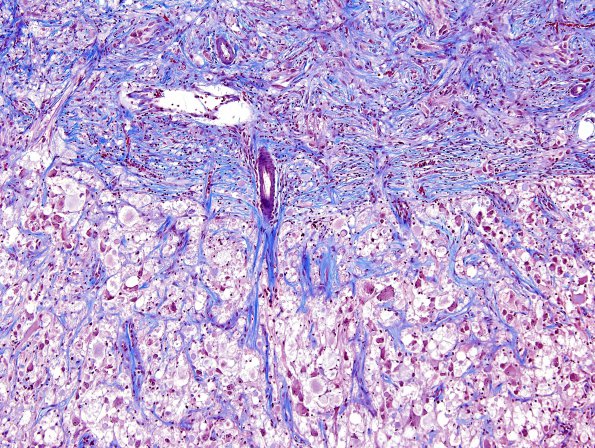

Washington University Experience | NEOPLASMS (NEURONAL) | Ganglioglioma | 8G1 Ganglioglioma (Case 8) Trichrome 6

8G1-3 A trichrome stain highlights the overlying leptomeningeal invasion and fibrosis which extends along the Virchow-Robin spaces and strikingly identifies eosinophilic granular bodies